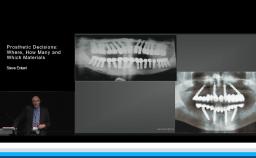

Dental implants are designed to provide support, stability, and retention for dental prostheses. In addition, implants have evolved to enable optimal esthetic and functional outcomes for patients seeking dental rehabilitation for a variety of indications. This lecture focuses on optimizing prosthodontic outcomes for patients via a systematic and evidence-based team approach to treatment. This includes contemporary treatment planning with an emphasis on communication of ideal implant placement; choice of implants, components, and restorative biomaterials to minimize complications; and prosthesis design and maintenance options to enhance longevity.

- recognize contemporary implant and prosthodontic components and their influence on ability to achieve optimal prosthodontic outcomes

- apply contemporary evidence-based prosthodontic protocols to comprehensive treatment strategies for a range of partially and completely edentulous indications